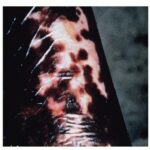

Several different skin manifestations can become apparent during the course of onchocerciasis. Onchocercal depigmentation or “leopard skin” is rarely associated with pruritus and is one of the most common skin manifestations of onchocerciasis. Hypopigmented patches with perifollicular spots of normally pigmented skin, typically occur symmetrically on the pretibial area of older people in endemic areas